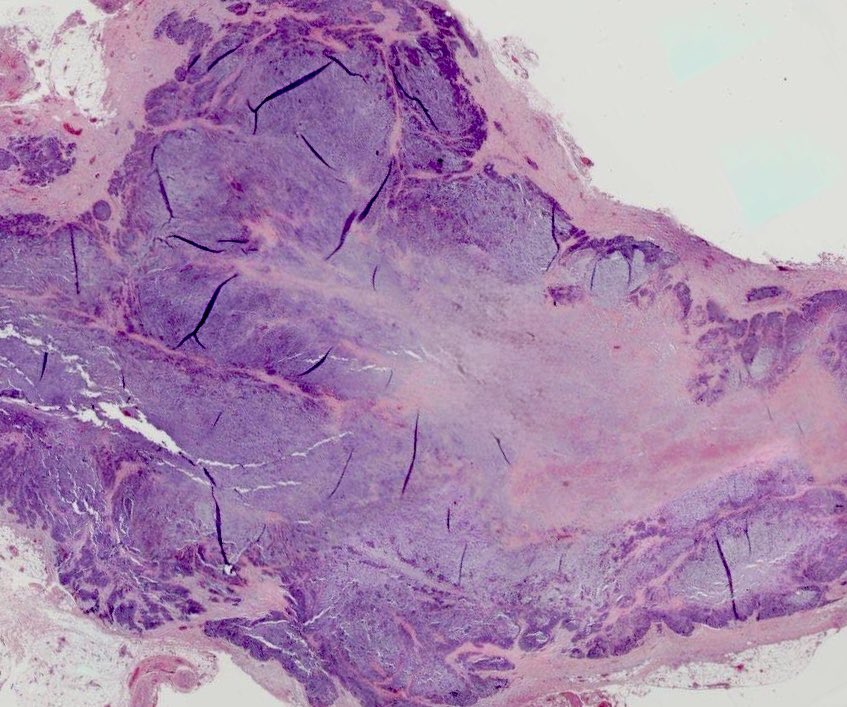

Biopsy of hard painless submandibular gland from a 60ish yr old man. What are the immunostains and what’s the likely diagnosis?#ENTpath #PathTwitter @HeadandNeckPath

This is myoepithelial carcinoma arising in a long standing recurrent submandibular pleomorphic salivary adenoma with a CHCHD7::PLAG1 fusion. This gene fusion has no therapeutic target but confirms it’s a genuine ca-ex-PA, rather than de novo myoepithelial ca #Pathtwitter #ENTpath